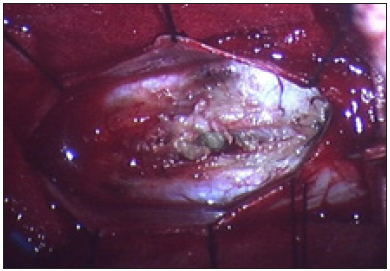

A 37-year-old woman presenting with low backache, and progressive weakness of both lower limbs for 5 months. On clinical examination, she had features of a conus medullaris syndrome with grade 4 power in both lower limbs, positive Babinski sign bilaterally, while abdominal reflexes and anal tone were normal without tuft of hair or a patent dermal sinus tract. A magnetic resonance imaging MRI showed cord expansion at the tip of the conus medullaris with a heterogeneous lesion hyperintense on T1 and hypointense on T2 images. In addition, contrast enhanced images with gadolinium revealed an intramedullary lesion at T12 L1 segment (Figure 1). After laminectomy, a midline myelotomy was performed and revealed a whitish and yellowish mass with a well-defined adherent capsule to spinal tissue followed by micro-dissection of the cyst wall allowing complete removal of caseous cystic contents with adequate conus decompression (Figure 2). Pathological examination confirmed the diagnosis of dermoid tumor, showing stratified squamous epithelial cells with underlying fibrous connective tissue containing hair follicles, keratin and sebaceous glands. The patient recovered well from the procedure, her back pain had not recurred, and she remained independent postoperatively.

Figure 4: Operative picture showing the midline myelotomy with expression of the keratinous sebaceous content of the cyst (black arrow).